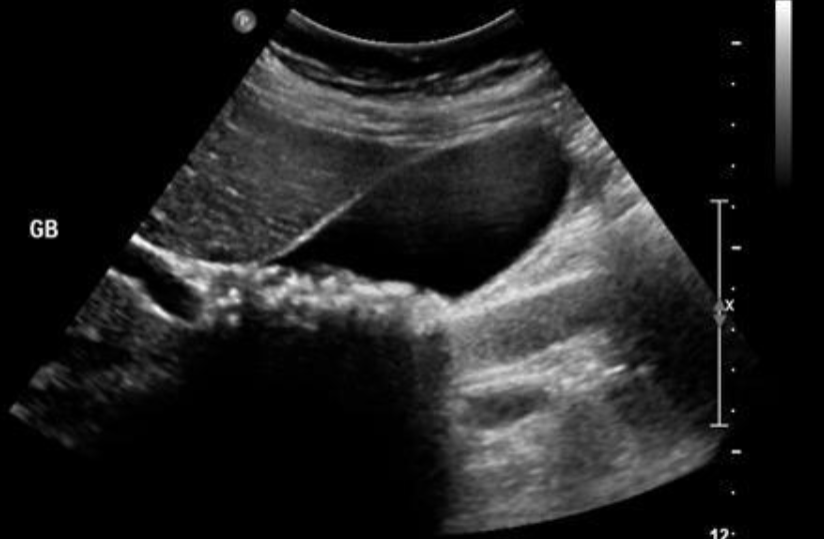

US—distended GB & cystic duct w/ stones, thickened wall, sonographic Murphy’s, pericholecystic fluid

Acute Cholecystitis

Thickened wall, double wall sign, sludge & stones with acoustic shadowing